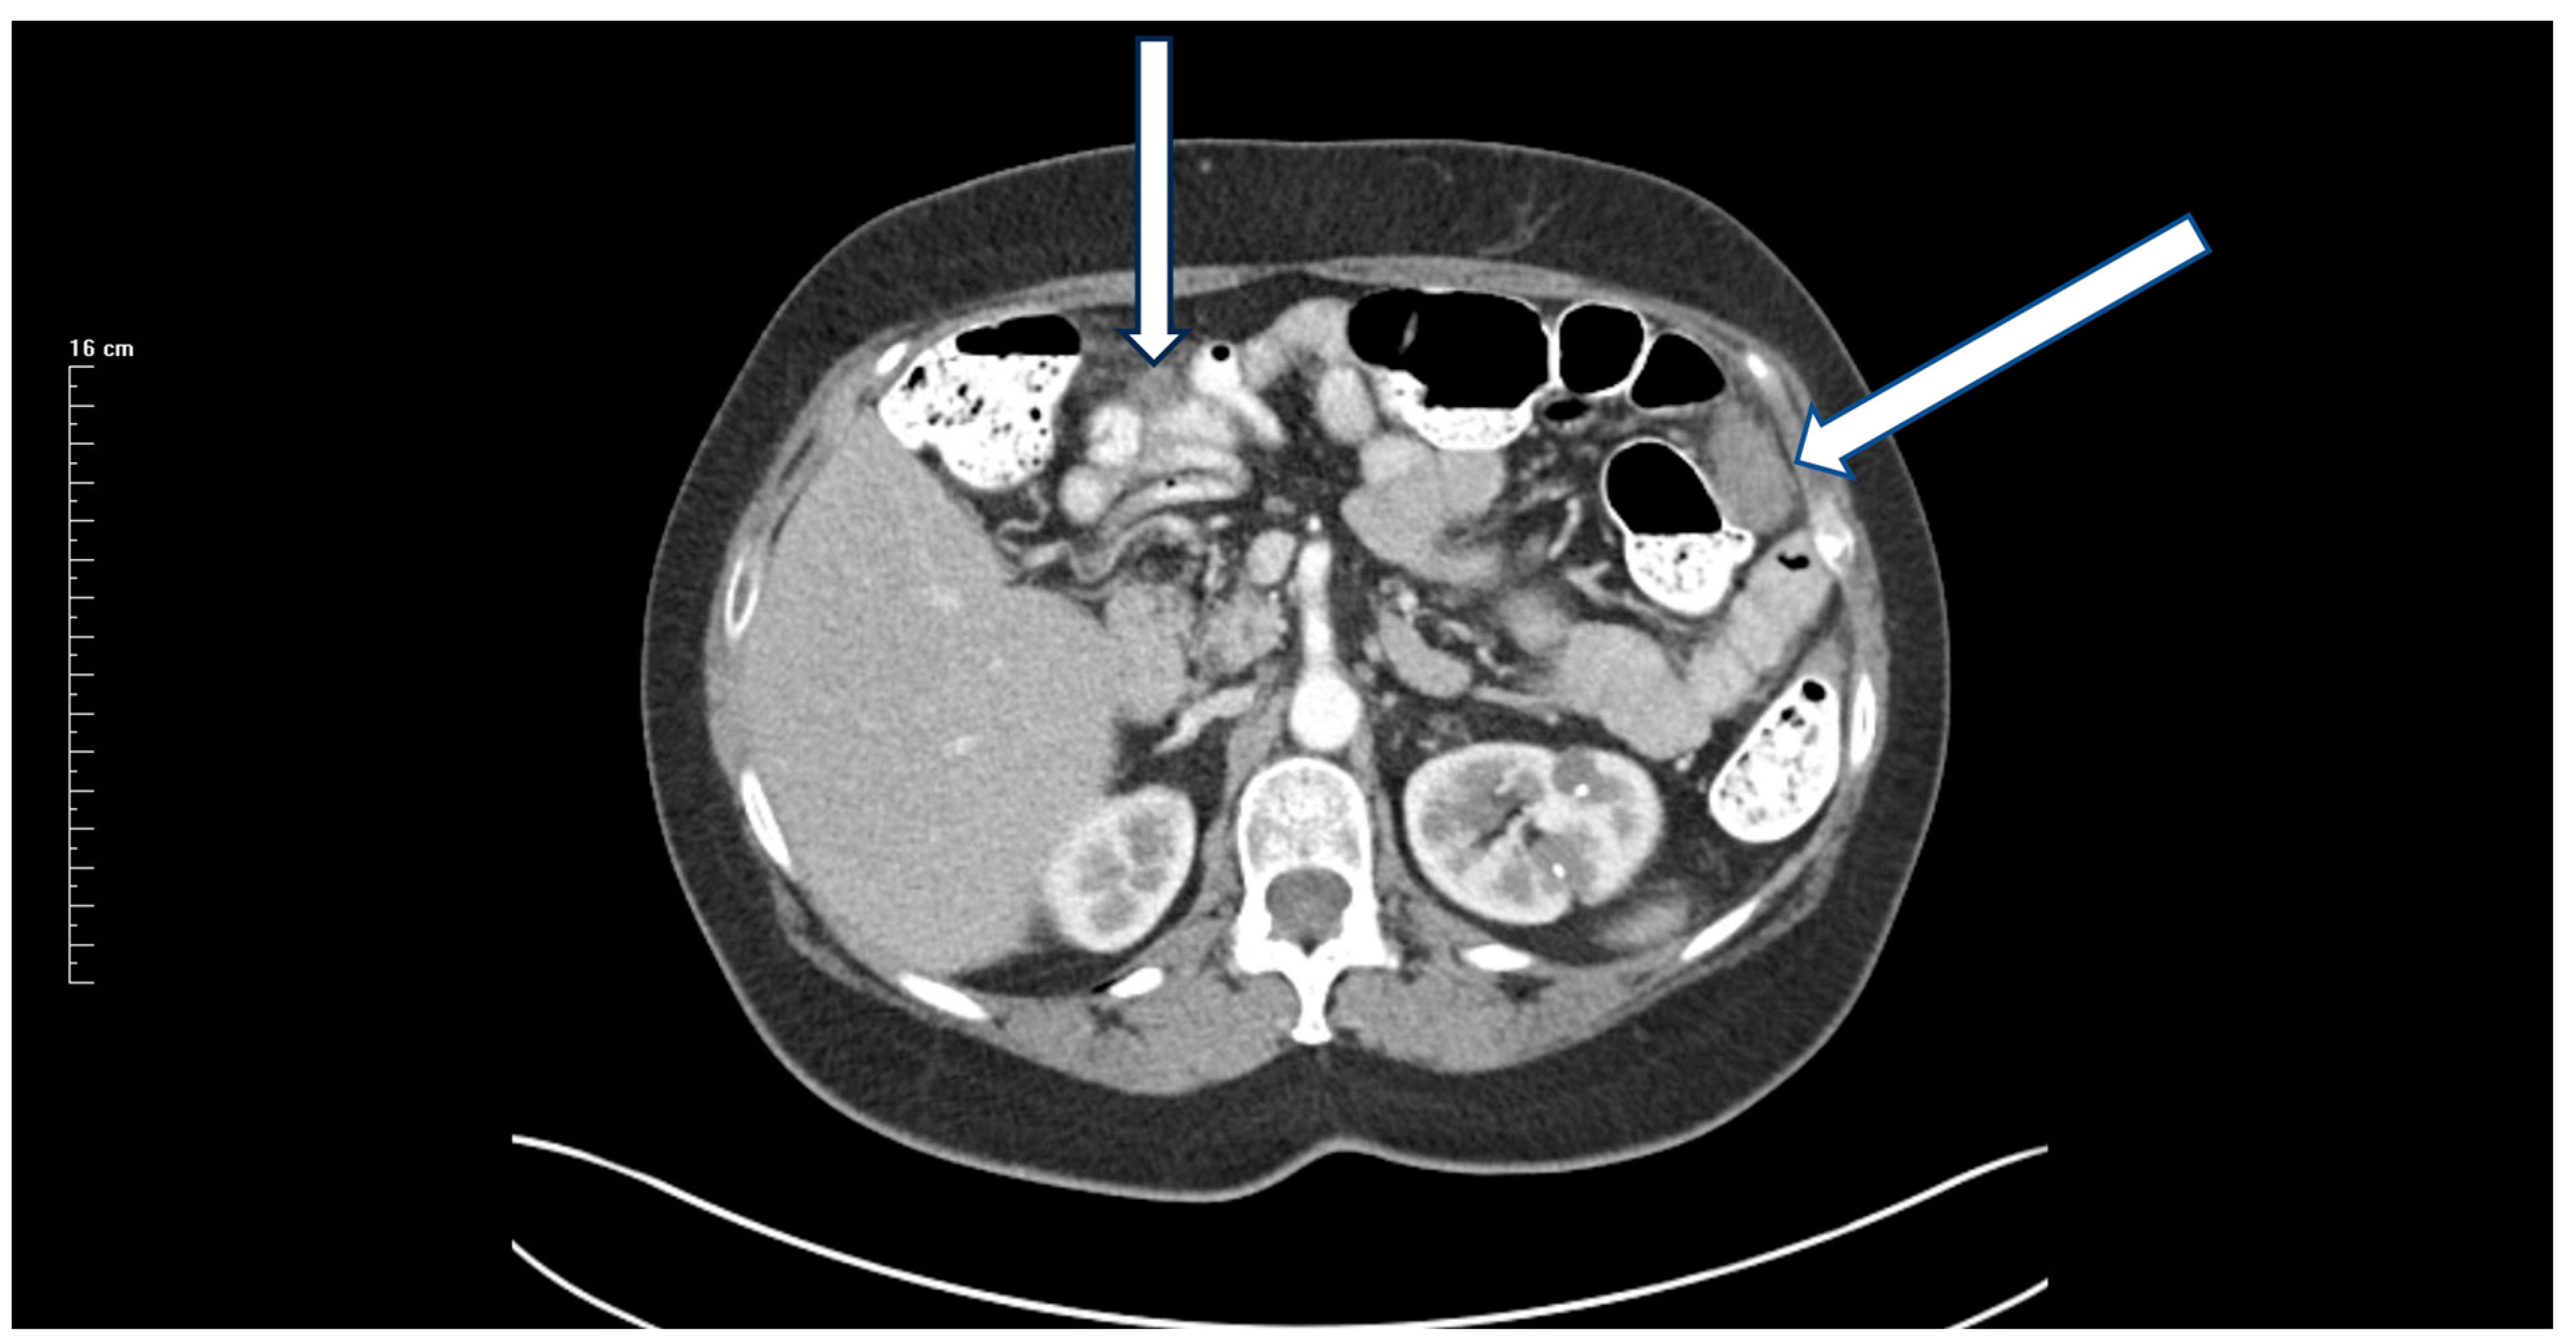

13 December 2017: Preoperative CT showed an 8 cm mass (Figure 1).

Figure 1. CT of a right-sided primary colonic mass that measures 8 cm in its greatest dimension. The external surface of the mass is irregular, suggesting peritoneal thickening. The medial aspect of the mass abuts the duodenum and no fat plane separating the mass from the second portion of the duodenum is evident. The mass penetrates posteriorly toward the right common iliac artery without obvious obstruction of the right ureter. A fat plane between the posterior aspect of the mass and the psoas muscle is present. No obstruction or perforation of the bowel above the mass exist. A single 1.5 cm lymph node is enlarged at the medial aspect of the mass. No additional systemic or local–regional manifestations of the cancer are evident. Radiologically, the mass is staged as T3/T4, N1, M0 with transmural extension through the wall of the intestine.